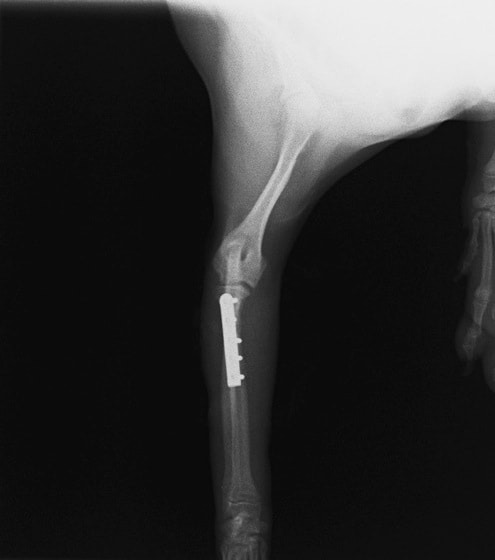

橈尺骨骨折 : 症例1 | 症例2 | 症例3 | 症例4 | 症例5 | 症例6 | 症例7

: 症例8 | 症例9 | 症例10 | 症例11 | 症例12 | 症例13 | 症例14

: 症例15 | 症例16 | 症例17 | 症例18 | 症例19 | 症例20 | 症例21

当院ではAdvanced Locking plate system(ALPS)と、Locking compression plate system(LCPS)という骨接合法で骨折症例の治療を行っています。

LCPは、スクリュー(ネジ)とプレート(金属の板)をロックする特殊な構造により骨折部位を固定する新しい世代のプレートシステムです。ひとつのホールでロッキングスクリューとスタンダードスクリューの使用を選択できるユニークな構造をしているため、骨折断端間の圧迫を目的とした従来型プレート固定法に加え、高い角度安定性を有するロッキングスクリューを用いた固定法の選択が可能です。従来のプレートシステムでは困難だった部分の骨折や癒合不全の症例に高い治療効果をもたらします。

7.1.5mmと薄いプレートのため、超小型犬にも使用しやすい